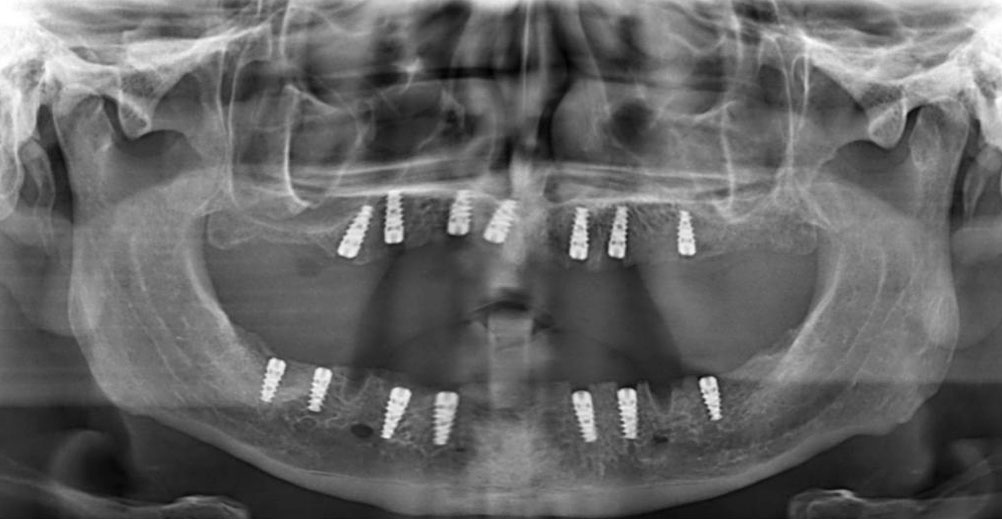

MPI All-In System®, modern dental implantolojinin tüm gereksinimlerini tek bir gövdede toplar. İster dar kretler ister sınırlı kemik yüksekliği olsun; All-In teknolojisi, hekime en zorlu anatomik koşullarda bile tam kontrol imkanı tanır.

Sinüs lifting veya kemik ogmentasyonu gibi ileri cerrahi müdahalelere gerek kalmadan, sınırlı dikey kemik mesafesinde güvenli ve estetik sonuçlar sağlar. Daha az cerrahi müdahale, daha hızlı iyileşme süreci ve yüksek hasta memnuniyeti.

Karmaşık vakalar için tek bir mükemmel çözüm: MPI All-In System®. Modern dental implantolojinin sınırlarını zorlayan bu sistem, her kemik tipinde yüksek performans ve klinik güven sunar.